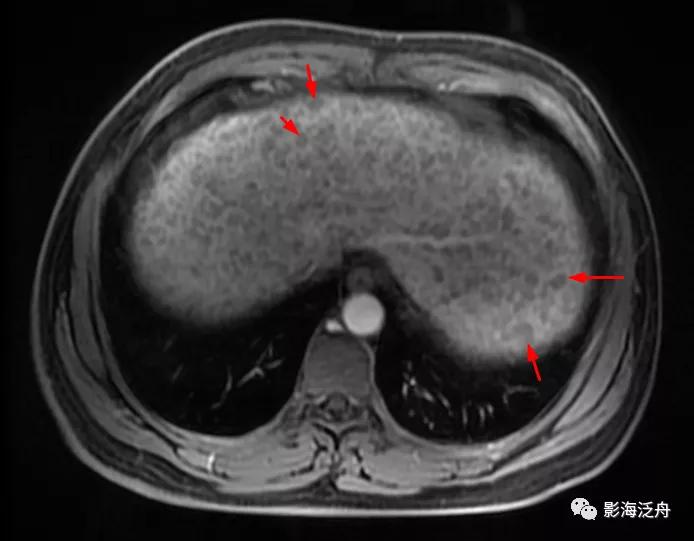

中年女性患者,皮肤黄染、瘙痒一月余前来就诊。能从这幅图像上发现什么问题吗?

将正常人与该患者的T2WI抑脂序列放在一起对比观察。在抑脂较均匀的区域,可以发现该患者肝实质的T2WI信号轻度增高(红箭),门静脉周围的胆管间隙增宽(绿箭),肝周间隙缩小(蓝箭)提示肝脏肿大,脾大(黄箭)。

上图特征不甚明显,需要反复对比观察。

增强动脉期,患者肝实质呈弥漫性斑点状强化(类似于粟粒型肺结核),这种强化方式可能与动脉及门脉的细小分支异常分流及部分肝组织灌注不良有关。门脉期及静脉期患者肝实质呈较均匀强化(未给出图像),提示病程相对可逆。

与正常人对比可以更好地观察上述图像特征,注意肝损伤患者的肝脏强化程度整体较低(以脾脏强化程度作为参照,两幅图像的强化时间大致相仿),但平衡期强化程度并无异常减低(未给出图像)。